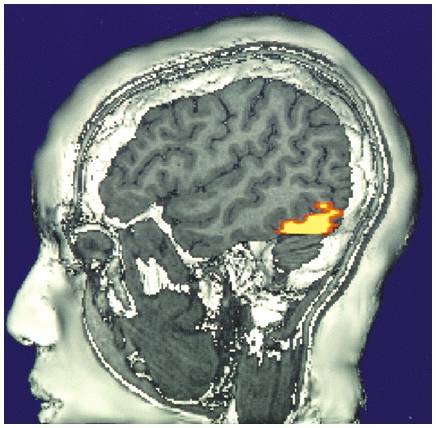

Visual Function

• Functional MRI scan shows the visual cortex activates as the subject looks at faces.